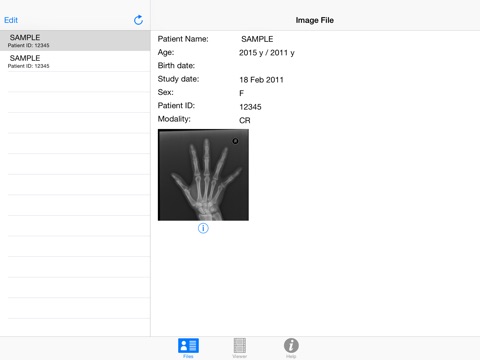

2. Get all the same information doctors get about your x-ray, like when did you take it, your age at the time, what kind of machine they used and so forth.